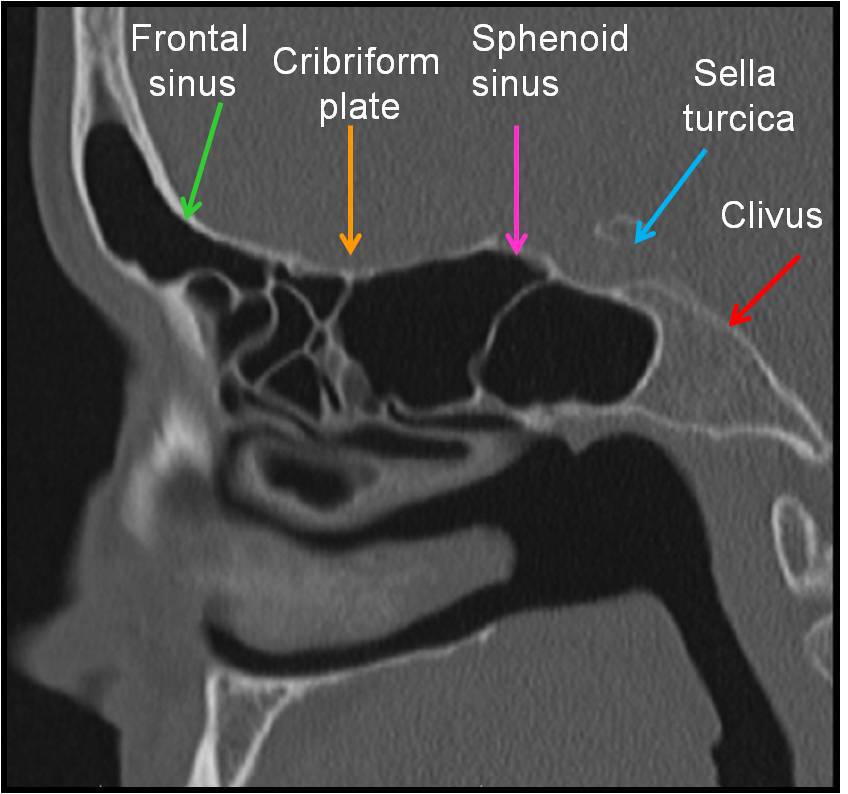

C – Cribiform plate (keros classification) – to assess the depth of olfactory fossa, length of lateral lamella, symmetry, slope or any dehiscence.

S – Sphenoid sinus – pneumatization, septations, dehiscence of carotid artery or optic nerve.

S – Skull base – dehiscence, slope (examine sagittal plane of CT scan)